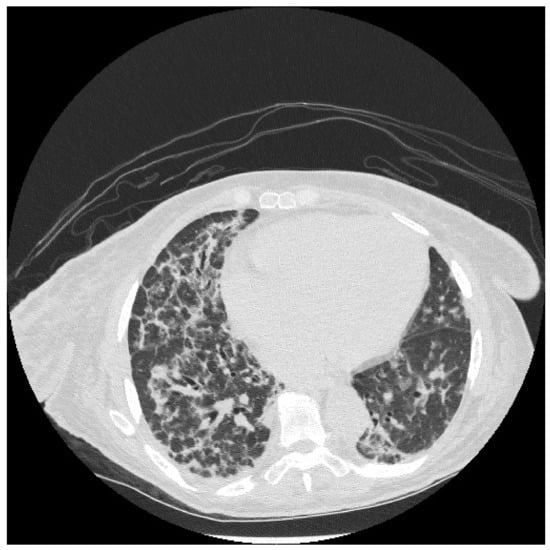

6.2. Histopathologic and Radiographic Findings in Myositis-Associated ILD